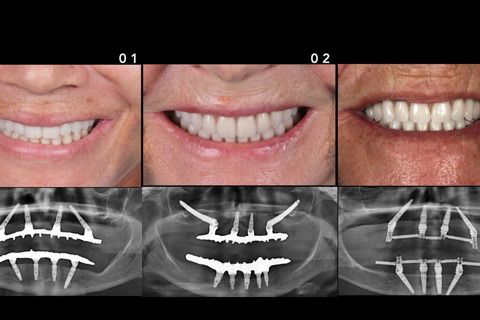

Resultado final imediato dos 3 casos clínicos

Foto 18 Resultado final imediato dos 3 casos clínicos